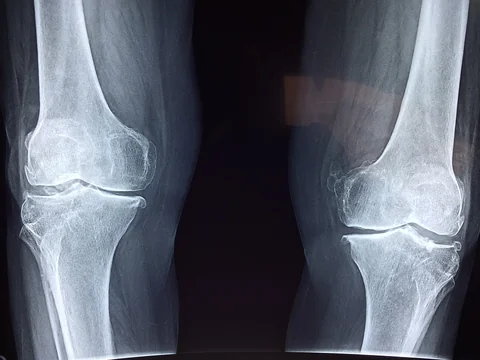

A medical evaluation is critical after a workplace injury because it will help treat your injuries and provide evidence for your workers' compensation claim.